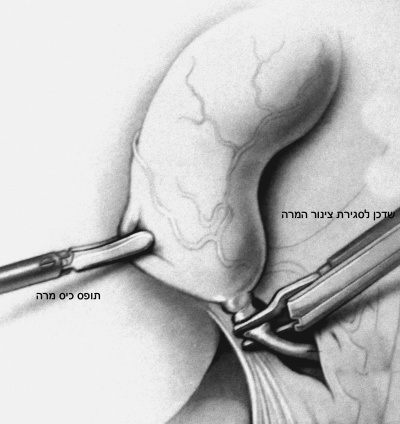

- בקו אקסילרי קדמי, בין ה- Anterior superior iliac spine לקשת הצלעות, דרכו מוחדר תופס כיס מרה שני המחזיק את כיס המרה בכיס הארטמן (איור 7.8).

לאחר שמזהים את כיס המרה בעזרת תופס כיס המרה, דוחקים את כיס המרה מעל לכבד, וכך הוא נשאר במשך כל הניתוח. צעד זה מאפשר זיהוי משופר של הציסטיקוס ועורק כיס המרה. בעזרת תופס כיס המרה השני תופסים את כיס הארטמן, ובעזרתו מושכים את כיס המרה וחושפים אותו (איור 8.8 ו- 9.8).

| איור 10.8: חשיפת הציסטיקוס (תמונה עליונה) וסגירת צינור כיס המרה על-ידי מכלב (תמונה תחתונה). |